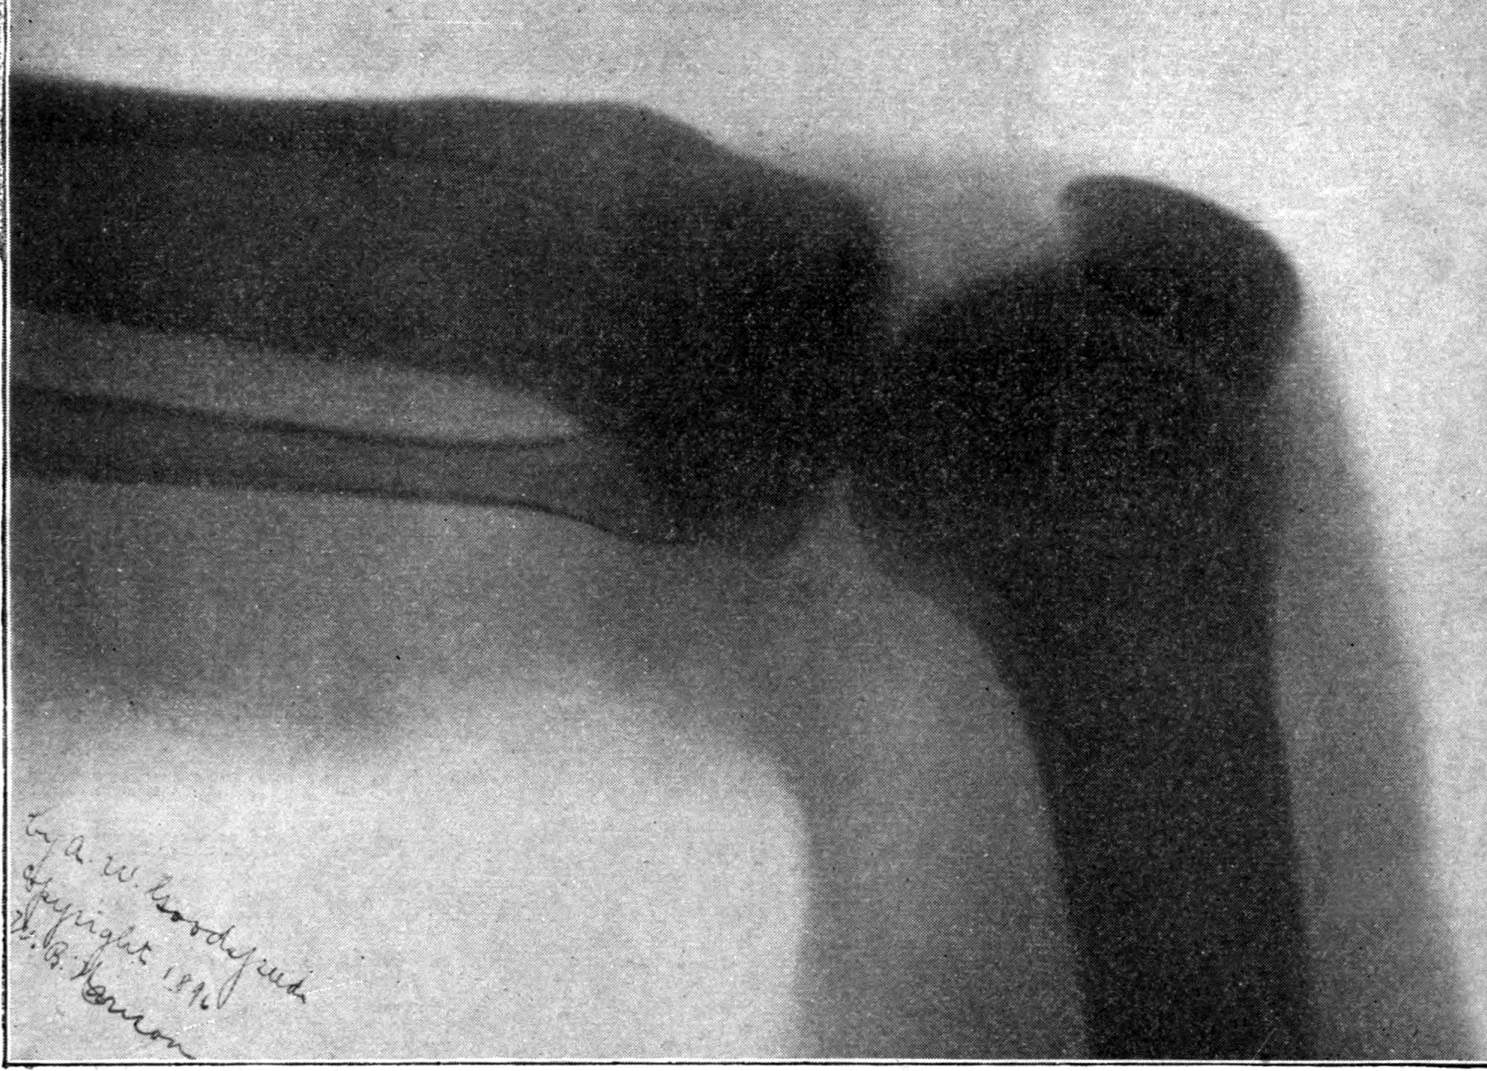

Fig. 2.—Broken Arm, Overlapping.

(Due to defective setting.)